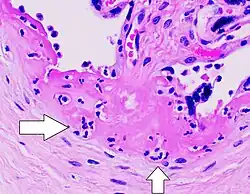

Intervellositis histiocítica crónica

La Intervillositis Histiocítica Crónica (CHI o CHIV, del inglés Chronic Histiocytic Intervillositis), también conocida como Intervillositis Crónica de Etiología Desconocida (CIUE) e Intervillositis Crónica Masiva (MCI), se define como una infiltración difusa de células mononucleares (histiocitos, linfocitos, monocitos) de origen materno en el espacio intervelloso dentro de la placenta. A menudo resulta en una severa restricción del crecimiento intrauterino que puede provocar un aborto espontáneo o muerte fetal. La tasa de mortalidad perinatal general es alta: 41%[6] a 77%.[7] La tasa de recurrencia también es alta: 67%[7] a 100%.[6]